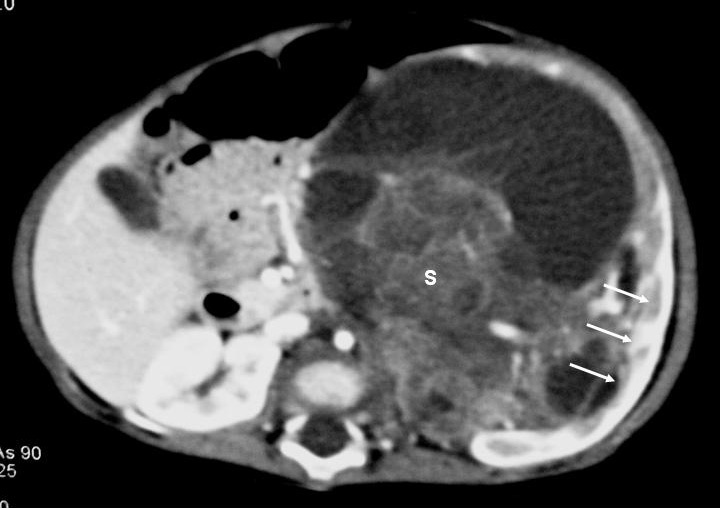

De los 11 nefromas mesoblásticos (con edad y presentación mostrados en la tabla 1) en 7 pacientes el tumor fue sólido y en 4 quístico, con presencia de un polo sólido. En 5 pacientes se encontraron áreas compatibles con necrosis, en dos sangrado intracavitario y en uno función excretora dentro de la masa. Siete pacientes tenían una colección subcapsular y 5 un anillo ecogénico periférico en la ecografía (figs. 1 y 2).

Fig. 2. Nefroma mesoblástico. Niña recién nacida con masa abdominal palpable, hipertensión arterial e hipercalcemia. (A) Ecografía abdominal. Corte renal longitudinal. Masa renal izquierda sólida, con colección subcapsular hipoecogénica (flechas negras). Resto de parénquima en polo inferior (flechas blancas). (B) Tomografía computarizada abdominal con contraste intravenoso. Corte al nivel del tercio medio renal. Masa renal hipodensa, con captación de contraste irregular, con anillo hipercaptante en la periferia del tumor (flechas blancas) y colección hipodensa subcapsular (C).

Los estudios de imagen muestran una masa por lo general de gran tamaño, sólida, que suele englobar el seno renal y puede contener, aunque no es frecuente, áreas quísticas, hemorrágicas y necróticas. No presenta buena delimitación con el parénquima sano y puede existir infiltración local de tejidos vecinos1. En uno de nuestros pacientes, estudiado por masa abdominal y cuadro clínico de obstrucción intestinal, se identificó una masa renal que infiltraba el colon, el bazo y la glándula suprarrenal. Un signo ecográfico característico es la imagen en anillos concéntricos hiper e hipoecoicos en la periferia del tumor5,7. En nuestra serie la ecografía demostró una colección hipoecoica subcapsular en 7 pacientes y anillo ecogénico periférico en 5.